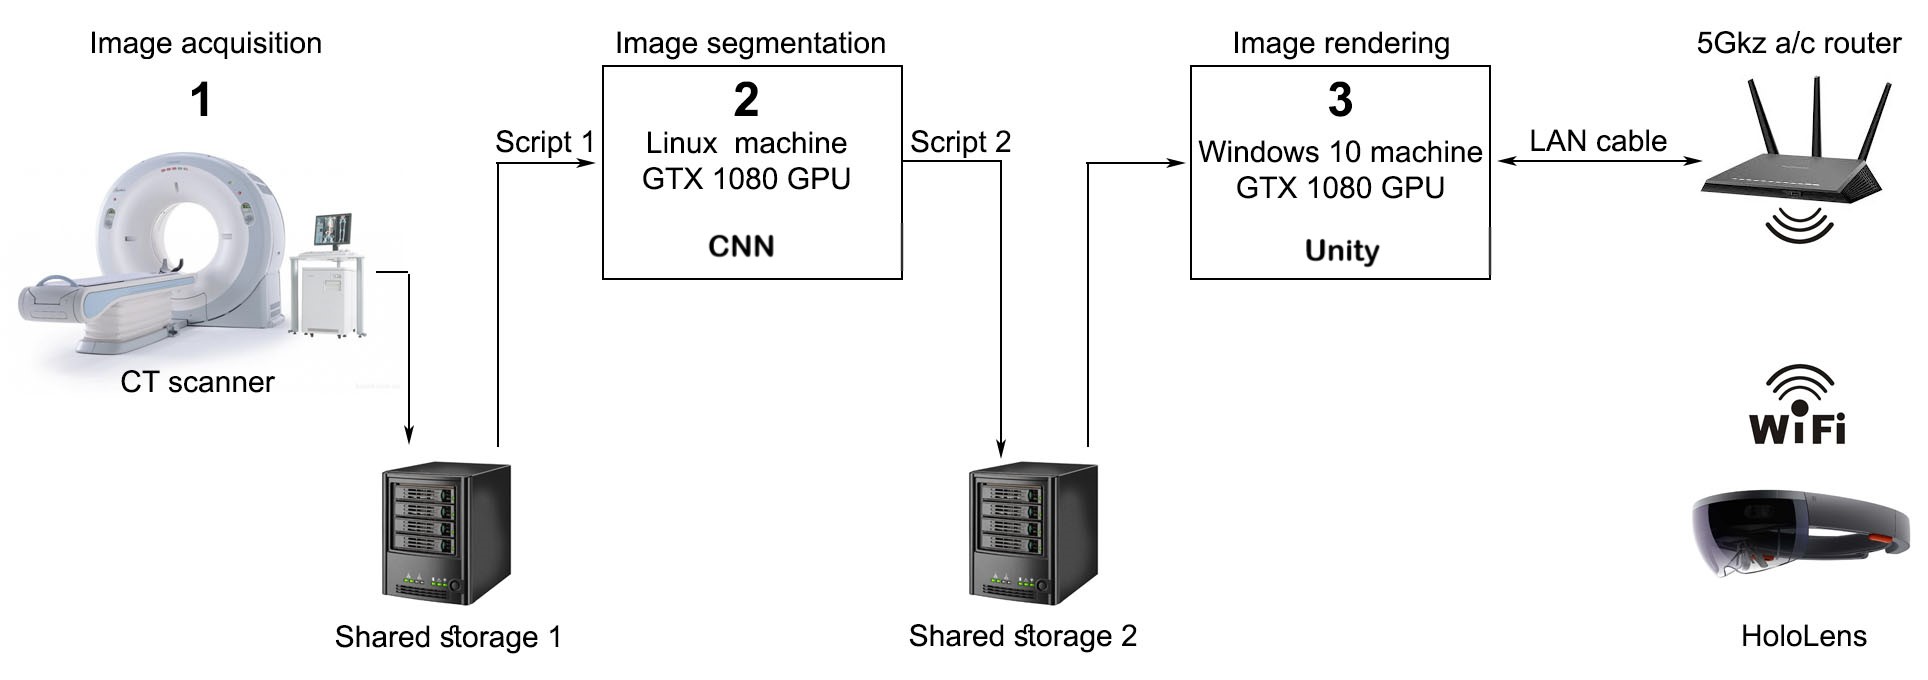

In Figure 1.3, we present a general overview of the pipeline we propose. The CT scans acquired by the CT scanner [Figure 1.3(1)] are stored in Shared storage 1. Script 1, running on the Linux machine [Figure 1.3 (2)], continuously monitors Shared storage 1, and queues a new liver segmentation job as soon as it detects a new CT scan. Script 2, running also on the Linux machine, manages the new segmentation results: as soon as a new segmentation result is available it copies it in DICOM format on Shared storage 2 for classic visualization, starts the file conversion and copying procedure towards the Unity engine format, and optionally sends an update email to interested parties that a new segmentation result is available on Shared storage 2. Shared storage 1 and Shared storage 2 can use the same physical hardware. Further, a 3D volumetric image rendering server based on the Unity game engine and running on the Windows 10 machine [Figure 1.3 (3)] powered by one or more high-end NVIDIA GPUs connected in SLI, renders the 3D volumetric image liver segmentation, encodes the video frames and sends them, through the 5Ghz 802.11ac router, towards the HoloLens Client for visualization and manipulation as a mixed reality 3D volumetric image. Through the UI, the user can browse, load or unload for visualization the liver segmentations already prepared in Unity format on Shared storage 2 by the Script 2 running on the Linux machine.

The advantage of having two dedicated machines is twofold: as both the 3D visualization and the medical volumetric image segmentation using a CNN are resource-intensive, the visualization performance will not be affected by a (possibly overlapping) running segmentation (ensure no hardware resource sharing), and also, the machine learning works at its best on Linux. Our experiments have also shown that for best latency, the router should be a model capable of running in the 802.11ac WiFi standard at 5Ghz, and channel bandwidth should be set as large as possible (we used 80Mhz).